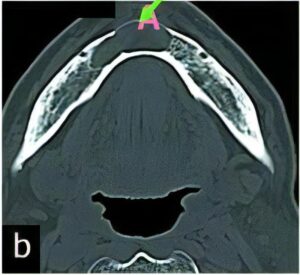

のう胞

のう胞は、何らかの理由で“水を含んだふくろ”ができてしまう病気です。特に顎骨は、のう胞ができやすいと言われています。

顎骨ののう胞では、虫歯から発生する「歯根嚢胞」が大半を占めていますが、くちびるにできる「粘液嚢胞(唾液が貯まった嚢胞)」や「含歯性嚢胞(埋伏歯にできる)」など様々な種類があります。

当科ではCT、MRI、病理組織診(良性悪性の確認検査)などの検査・診断、および治療(手術)を行っています。